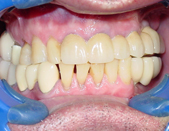

The term ‘Dental Implants’ refers to the surgical placement of artificial roots which help replace missing or badly damaged teeth. Other methods to replace missing teeth include dentures or bridges. The advantages of Implant tooth restoration is that it presents a more permanent solution.

The advent of Dental Implants removed the need to cut down adjacent teeth to restore a missing tooth. In most cases an implant can fill out the missing space and restore the esthetic look of the area with no collateral damage. The adjacent teeth can live happily ever after, instead of needing to support a missing tooth, they now can enjoy the support of the adjacent implant crown.

The placement of Implants involves a short surgical procedure, which requires placing a screw-like structure into the jaw bone. The Bone and Implant need to integrate, this takes about 3-4 months, the Implant Fixture and final Implant Crown can be fitted.